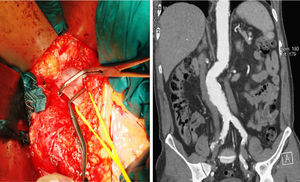

La duplicidad de la vena cava inferior constituye una anomalía anatómica infrecuente (0,3-3%). Tiene su origen en la regresión anómala de la vena supracardinal izquierda en el primer trimestre de embarazo. El diagnóstico preoperatorio en abordajes de región retroperitoneal minimiza el riesgo de hemorragia (fig. 1).

Caso clínico: varón de 70 años, fumador, con diabetes mellitus. Intervenido de forma programada de aneurisma aórtico abdominal de 5,2cm mediante incisión xifopúbica, con evisceración de paquete intestinal y apertura de retroperitoneo. Visualización de la vena cava inferior izquierda que cruza anteriormente sobre la aorta infrarrenal. Sección más ligadura de puente de unión entre ambas venas cavas. Disección e injerto aortoaórtico.